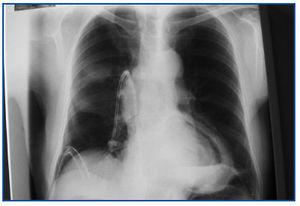

Este procedimiento se llevó a cabo con éxito en 4 pacientes, y se presentaron las siguientes complicaciones atribuibles al mismo: tres hemotórax, uno de ellos masivo, por lo que fue necesario practicar en cada uno de los pacientes toracotomía y tubo a tórax durante un promedio de 5 días; el paciente con hemotórax masivo requirió transfusión de 5 U de glóbulos rojos, mediastinostomía, ligadura de vasos sangrantes y toracotomía con tubo a tórax durante 7 días (figura 1 y figura 2).

Figura 2. Radiografía PA de tórax paciente D.